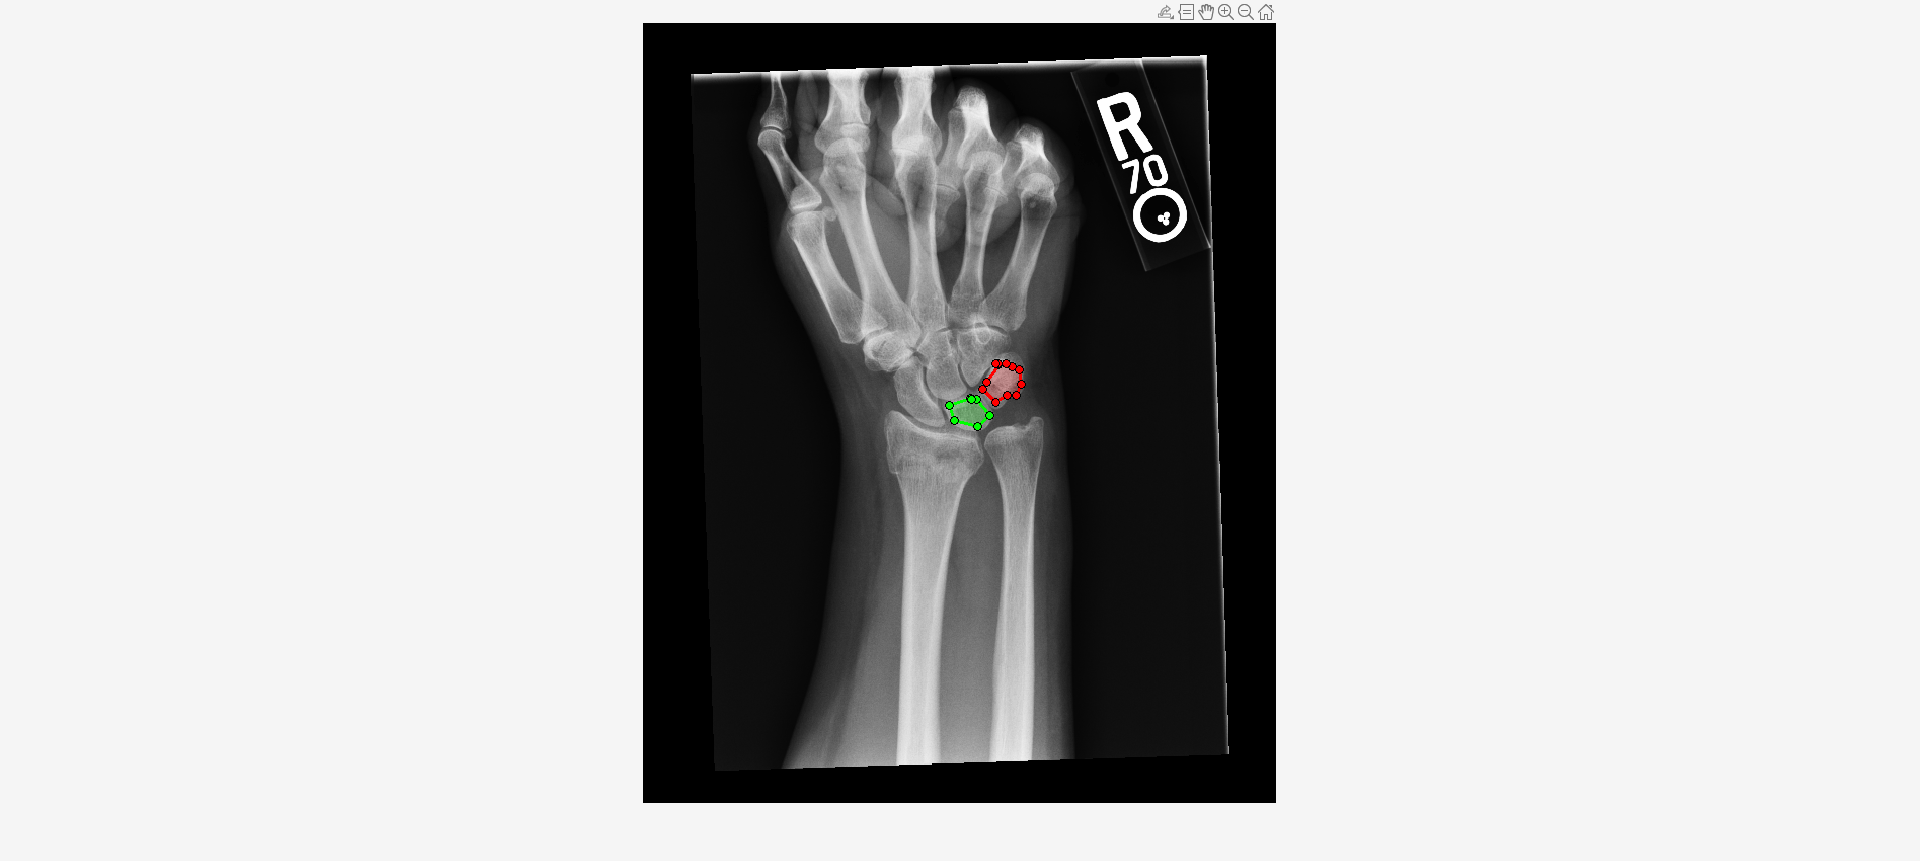

Load an X-ray image into the workspace as a medicalImage object. Visualize the image.

data = medicalImage("forearmXrayImage1.dcm");

I = data.Pixels;

figure

imshow(I,[])Draw two regions of interest (ROI) in the X-ray image. Create masks from the ROIs.

roi1 = drawassisted(Color="g"); roi2 = drawassisted(Color="r");

mask1 = createMask(roi1,I); mask2 = createMask(roi2,I);